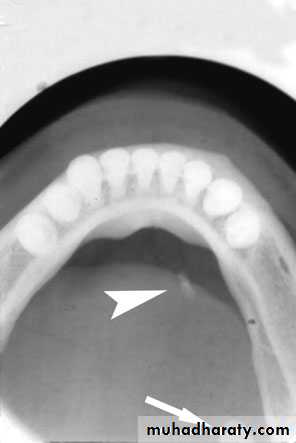

80% of sialoadenitis occur in sub mandibular salivary gland?80% is radio opaque stone.

Acute left submandibular sialadenitis.